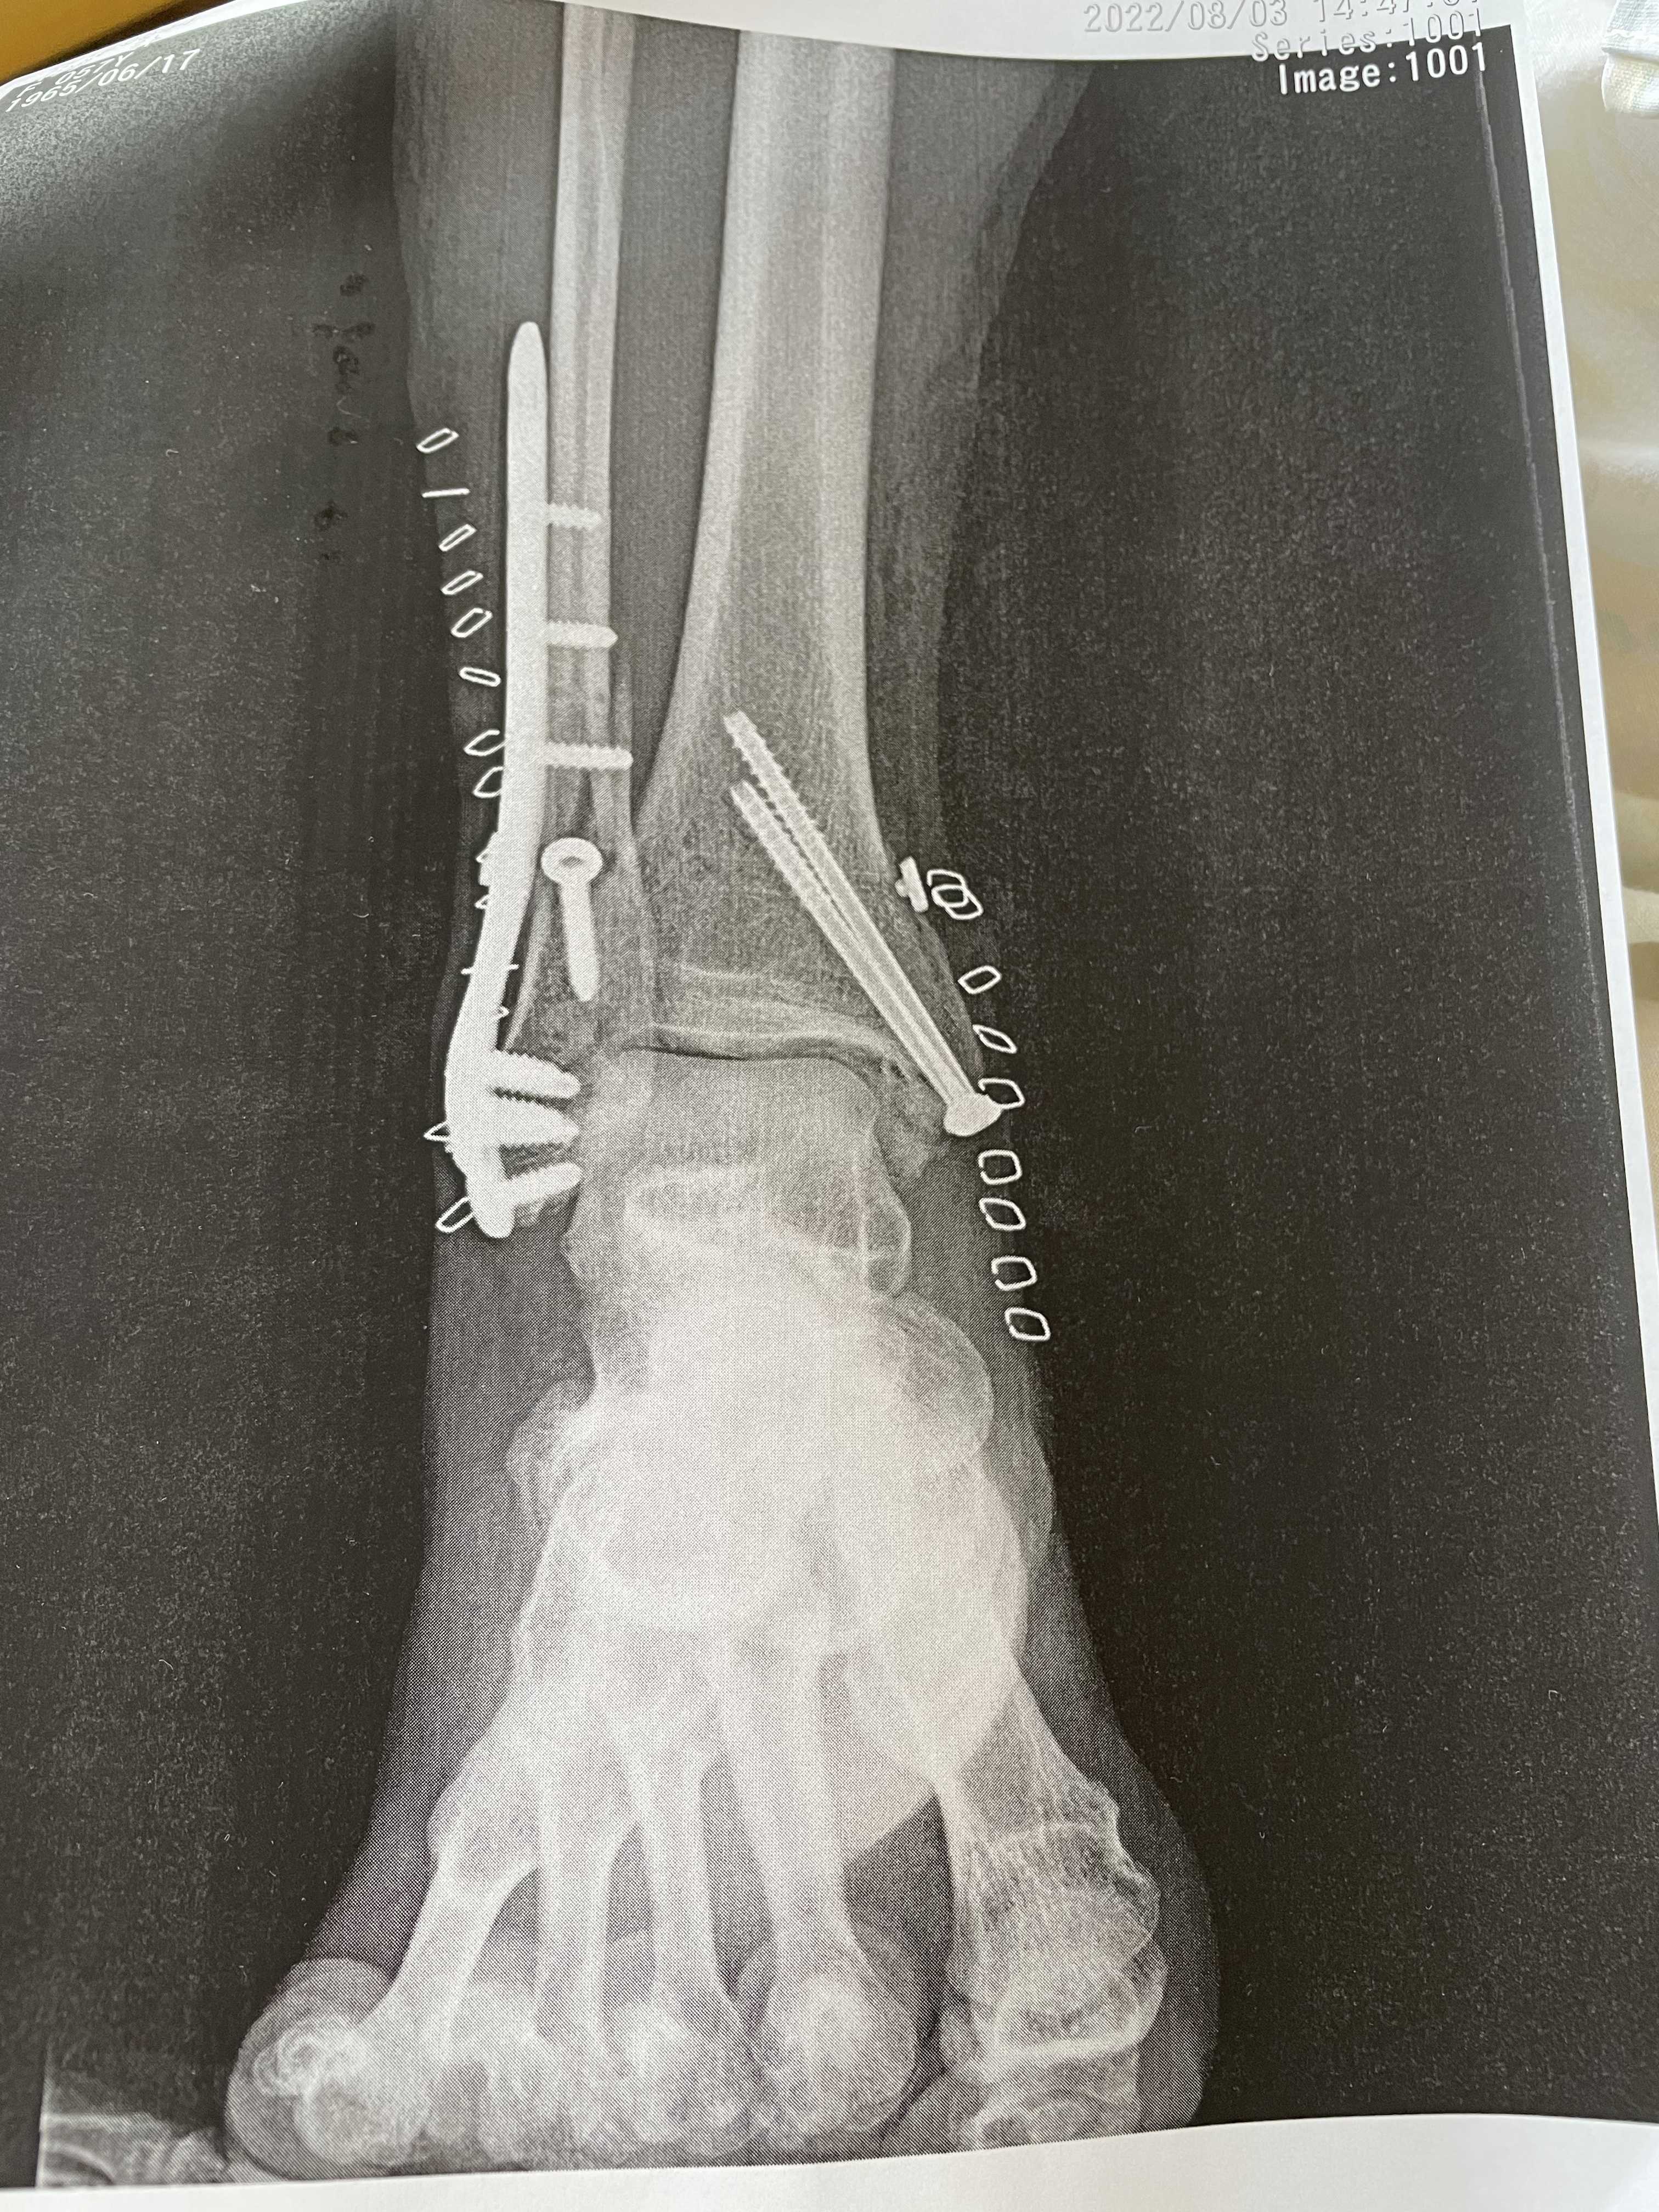

「右脚首関節脱臼骨折」

早目の処置が適正と言う事で先ずは脱臼を元に治し 翌日の8/3オペを行う。

所要時間麻酔から麻酔が切れるまで2時間。

三カ所の骨折でした。